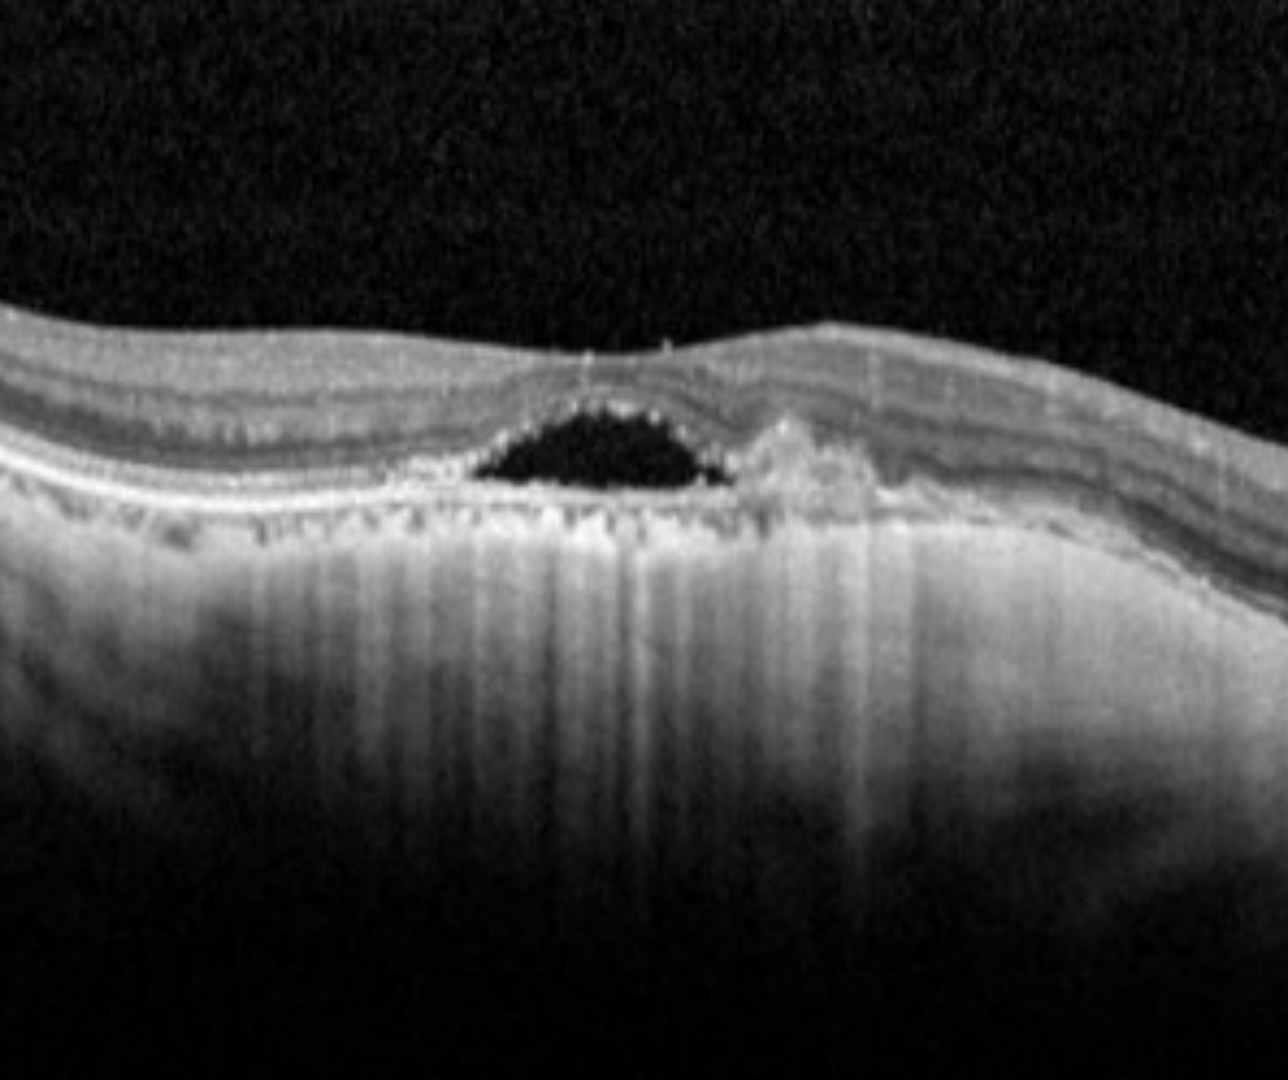

On OCT appears as a subretinal hyperreflective dome-shaped elevation with possible subretinal or intraretinal fluid. In the scarring phase, the lesion can become flatter and RPE hyperplasia may be seen. In the final atrophic phase, chorioretinal atrophy will be seen.

Spectralis OCT volume and line scans (right eye)

More info